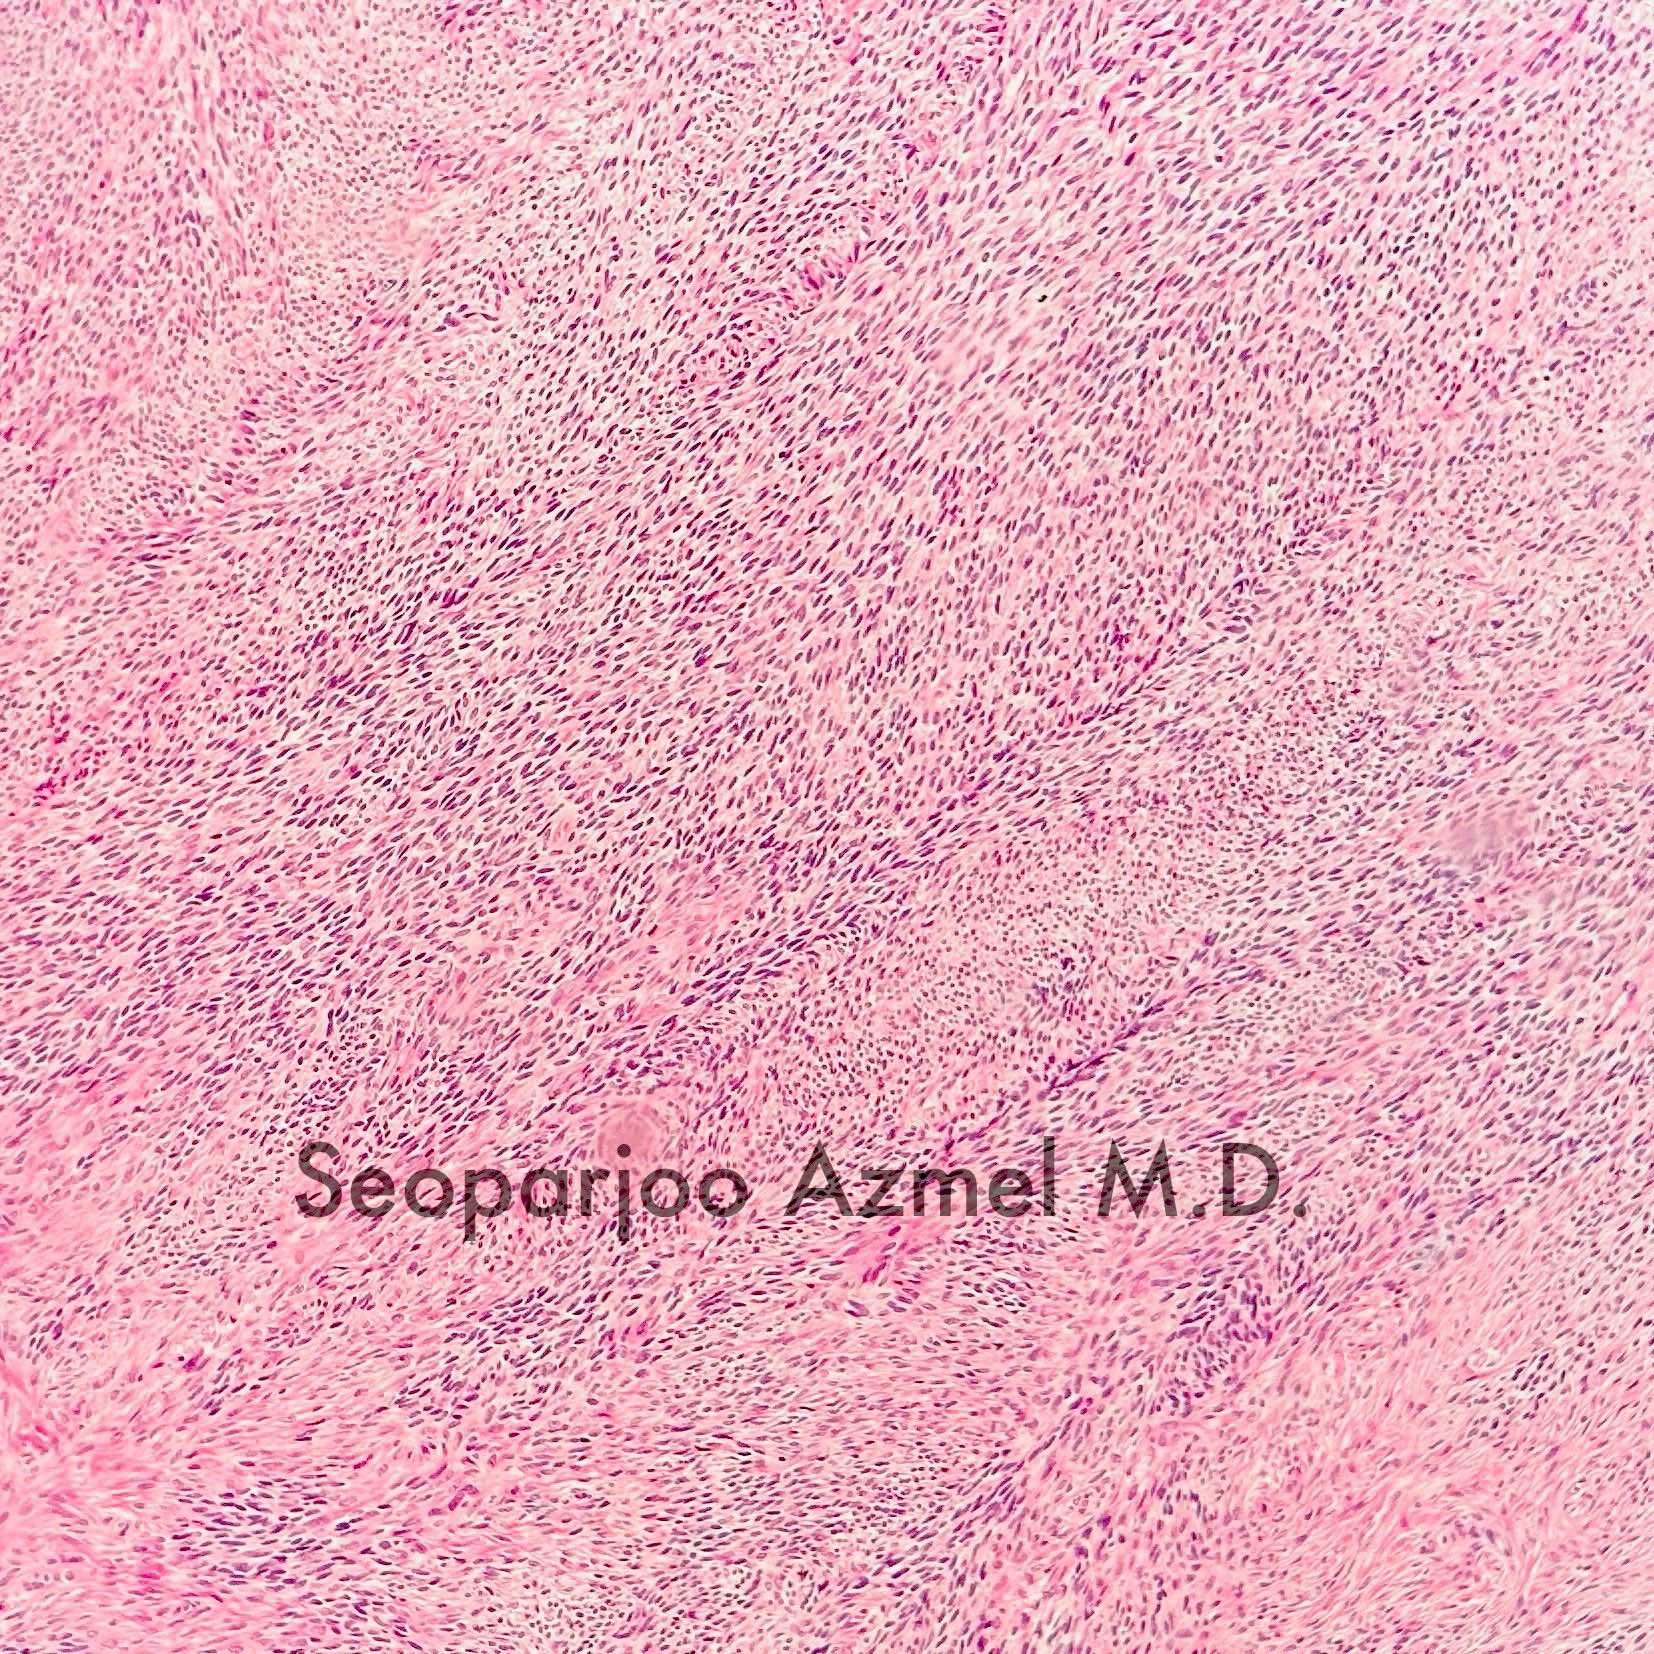

Microscopic (histologic) description

- Predominant population of cells showing ovoid to round nuclei and pale gray cytoplasm, which can be abundant

- Minor component of the tumor may have spindled nuclei, reflecting overlap between fibroma and thecoma

- Indistinct cell membranes impart a syncytial appearance

- Diffuse or nodular growth pattern

- Absent or minimal nuclear atypia

- Mitotic rate usually < 5/10 high power fields

- Hyaline plaques

- Cytoplasmic lipid vacuoles may be present but are not essential

- May show aggregates of cells with brightly eosinophilic cytoplasm (lutein cells)

- Calcification is more common in young patients (Int J Gynecol Pathol 1988;7:343)

- Uncommon features include keloid-like sclerosis, nuclear grooves, bizarre nuclear atypia (Am J Surg Pathol 2014;38:1023)

- Rarely contains a minor component of sex cord elements (Int J Gynecol Pathol 1983;2:227)

- Malignant thecoma: very rare, diagnosis requires diffuse moderate to severe nuclear atypia and high mitotic rate (> 4/10 high power fields) (Am J Surg Pathol 2011;35:e15)

Microscopic (histologic) images

Contributed by Victoria Collins, M.D., Tamara Kalir, M.D., Ph.D., AFIP and @SeoparjooAzmel on Twitter